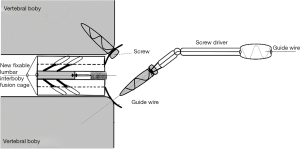

In ETDIF/PT-Endo-LIF technique, percutaneous pedicle screw implantation uses different approach from interbody decompression and fusion. Moreover, decompression and fusion are often accomplished by setting a 14-mm channel additionally. Decompression, interbody fusion and percutaneous pedicle screw implantation are not completed in a single 7.5-mm channel. PETOFPC overcomes the above limitations, and realizes one-stop decompression, fusion and fixation in a single 7.5-mm channel (Figure 16). The implementation of this technique requires the participation of a new integrated fixable and fused interbody cage (Figure 17).

PETOFPC technique innovatively sets screws from posterior corner in lumbar spine in a regular 7.5-mm diameter channel. PETOFPC is also performed in the posterolateral transforaminal approach (Figure 18). A cylindrical sheath with an outer diameter of 7.5 mm were inserted in sequence. Through the sheath alone or the endoscope, the intervertebral disk and cartilaginous endplate were removed while confirming through percutaneous endoscopic observation that no cartilage remained. At the completion of the endplate preparation, the new integrated fixable and fused interbody cage was inserted into the intervertebral space (16). Before the new integrated fixable and fused interbody cages were expanded, we should clearly expose the screw entry point in posterior corner. The screw entry point is the bony area between the pedicle and the endplate. When intervertebral height was restored, the two wings of new integrated fixable and fused interbody cage splay to the sides and fit to posterior corner in lumbar spine (Figure 19). In the single 7.5-mm channel, endoscopic visualization was used to monitor placing screws to make the new integrated fixable and fused interbody cage fixed in lumbar spine. The angles of screw placement were made up of inward inclined angle, head tilt angle and tail tilt angle, namely c1, c2, c3, a1, a2, a3, b1, b2 and b3, all which was measured and analyzed in this study.